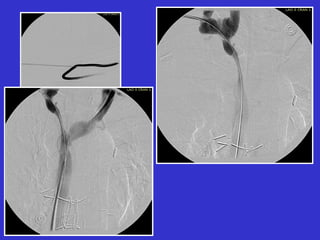

“ A well performed fistulogram is the

foundation for all percutaneous interventions ”

Thorough evaluation of the entire vascular access circuit

including the graft, native veins, and inflow arteries

Diagnostic Fistulogram

21 g butterfly needle

non-ionic contrast

multiple venous stenoses

Angioplasty Procedure

access

vascular

sheath

position

angioplasty balloon

across stenosis

fully inflate

balloon

stenosis

Post-PTA